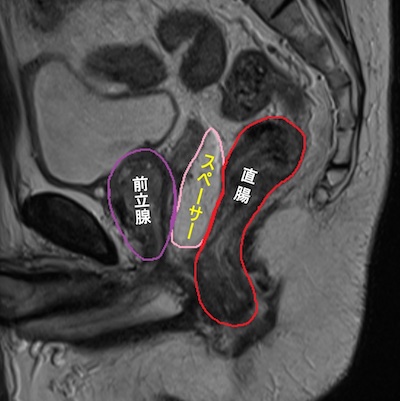

3.吸収性スペーサーによる直腸保護

人体に無害なゲルを挿入して前立腺と直腸を遠ざけます。治療期間中もMRIで確認し、直腸をしっかりと守ります。